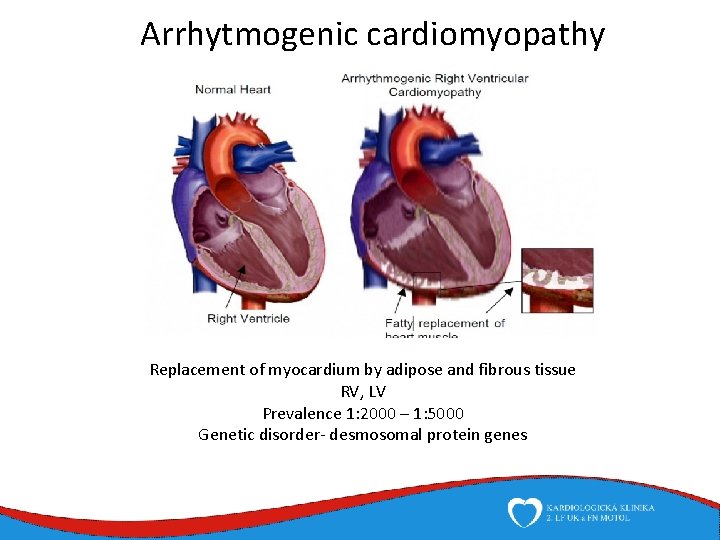

Arrhytmogenic cardiomyopathy Replacement of myocardium by adipose and fibrous tissue RV, LV Prevalence 1: 2000 – 1: 5000 Genetic disorder- desmosomal protein genes